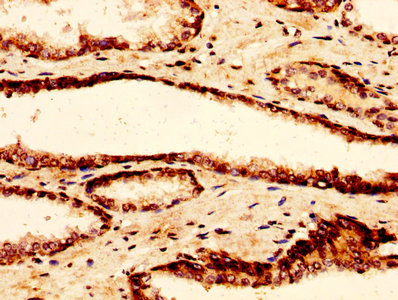

IHC image of CSB-PA010100OA07nacHU diluted at 1:50 and staining in paraffin-embedded human prostate tissue performed on a Leica BondTM system. After dewaxing and hydration, antigen retrieval was mediated by high pressure in a citrate buffer (pH 6.0). Section was blocked with 10% normal goat serum 30min at RT. Then primary antibody (1% BSA) was incubated at 4°C overnight. The primary is detected by a biotinylated secondary antibody and visualized using an HRP conjugated SP system.